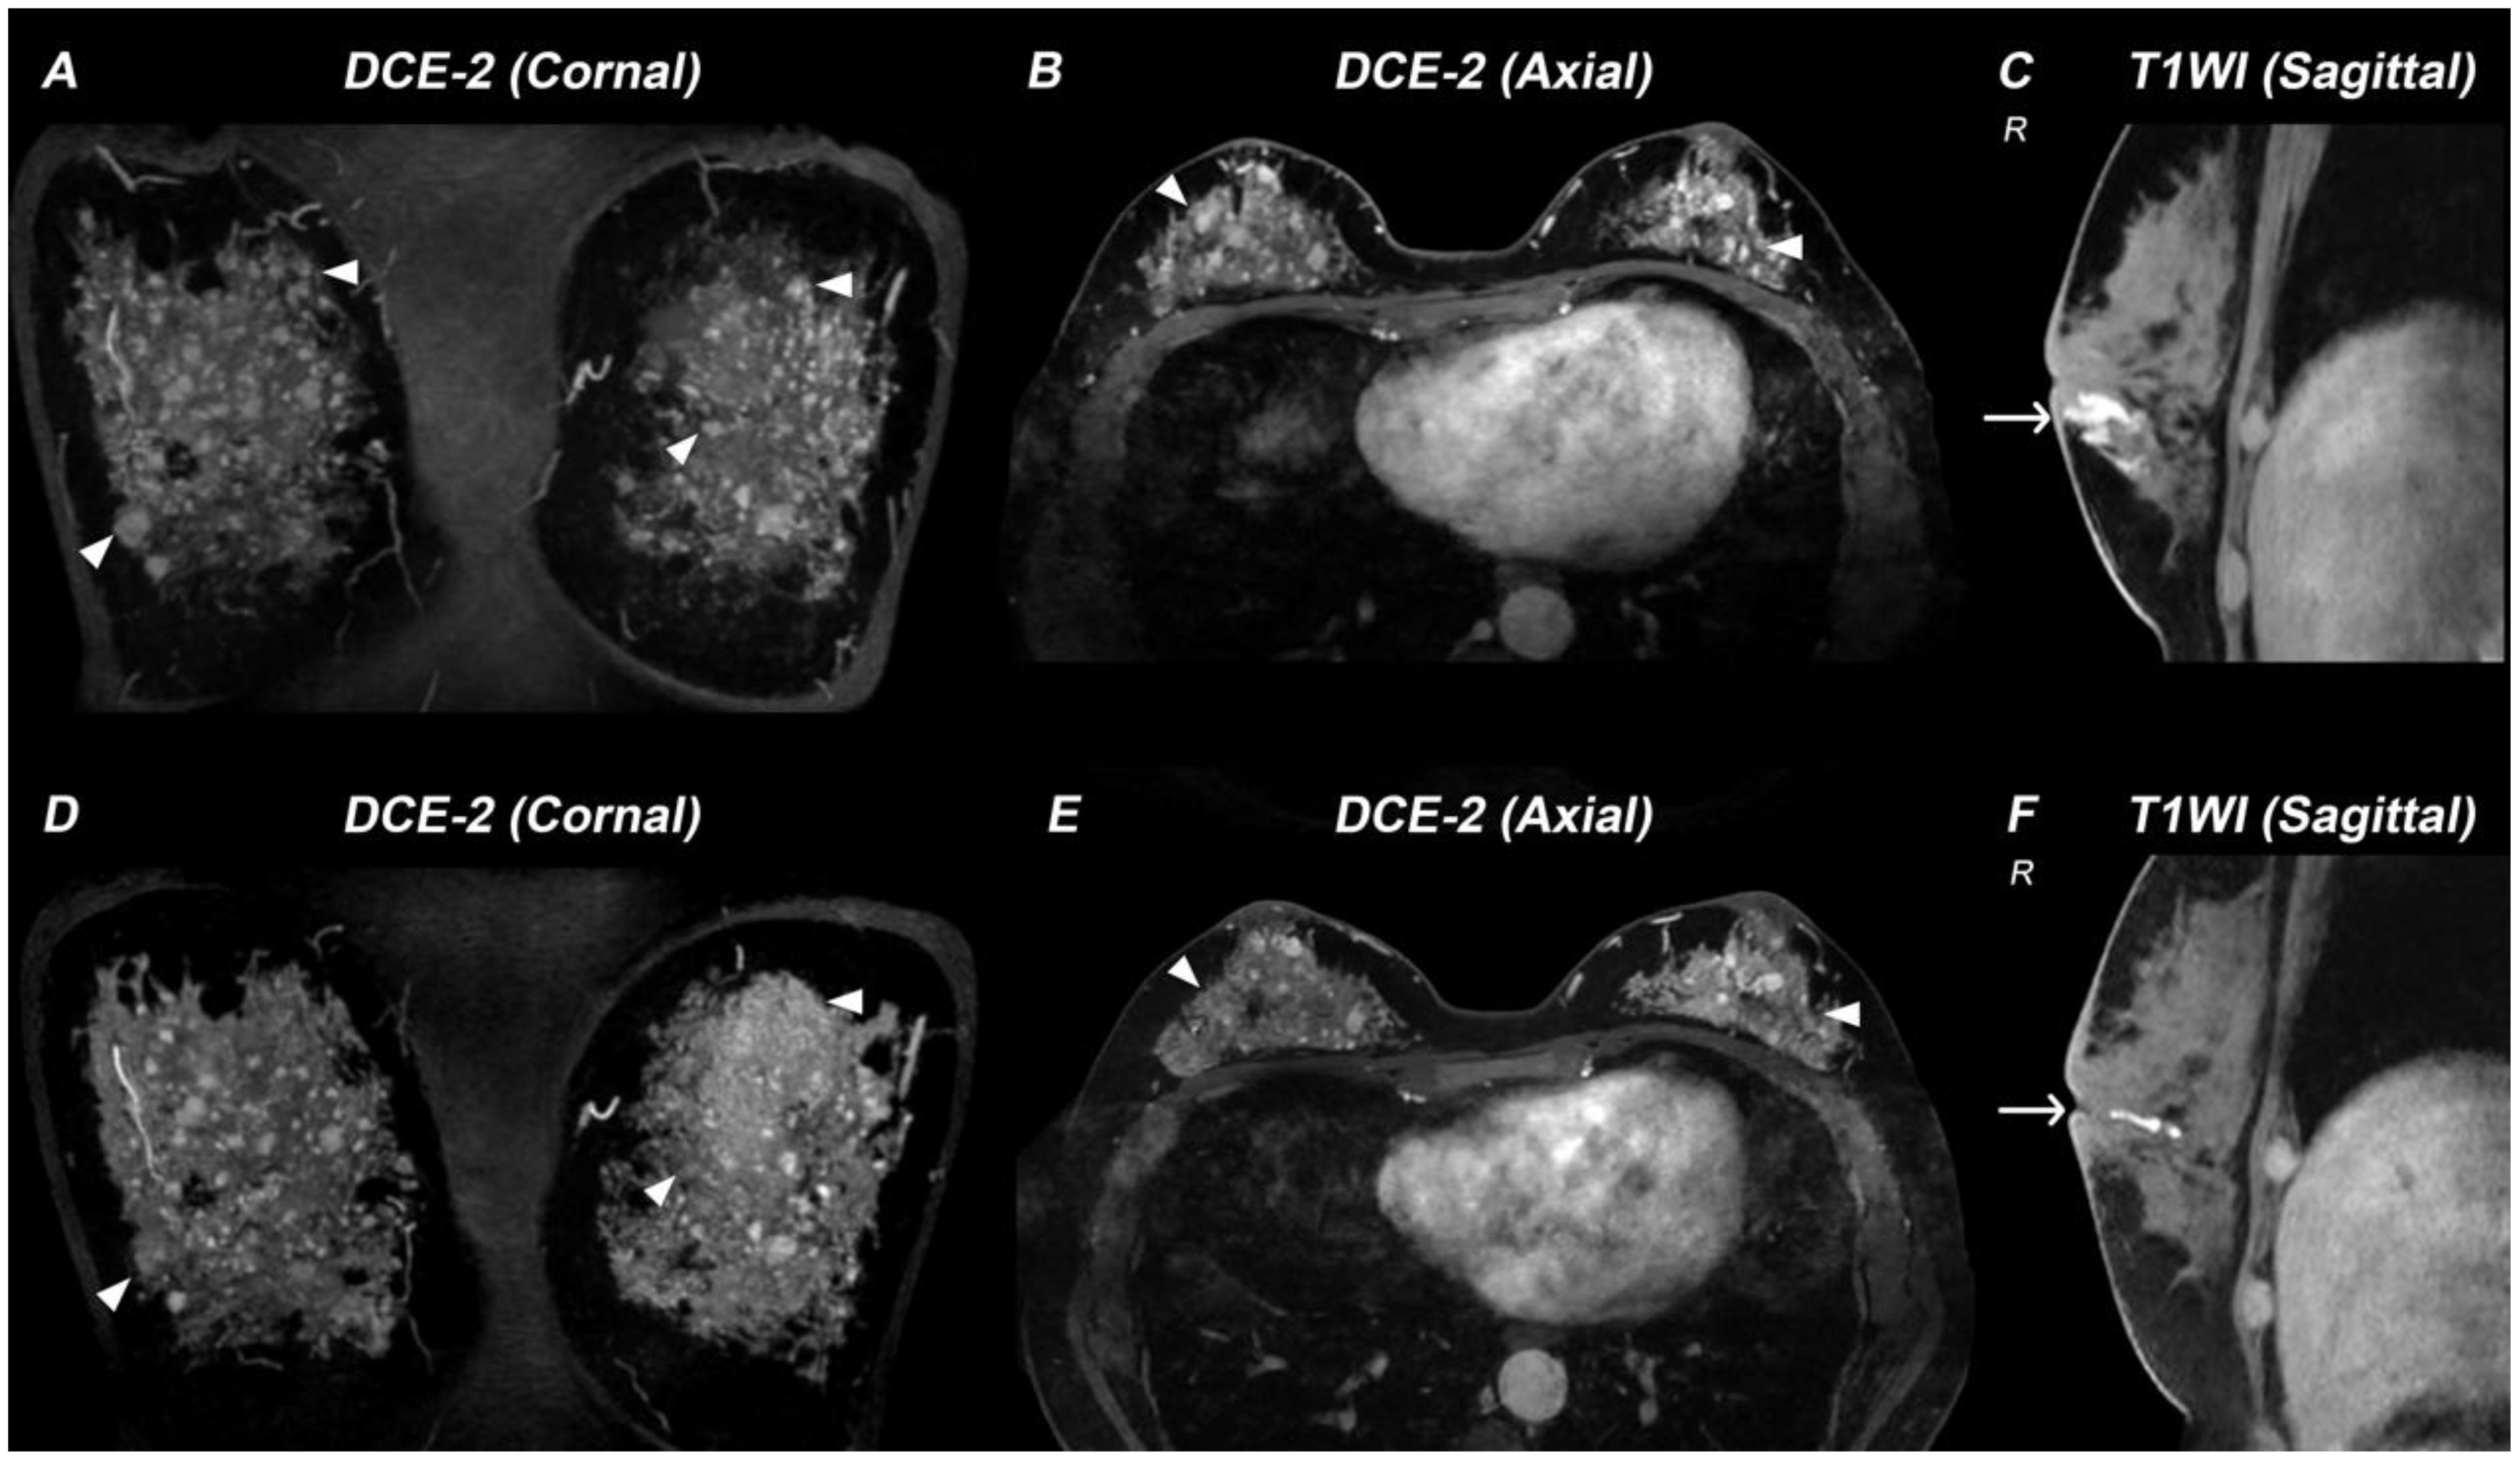

A 38-year-old woman (46,XX) presented with a 12-year history of bilateral breast nodules, having undergone two previous excisional biopsies that revealed intraductal papilloma and mammary duct ectasia (Supplementary Figure S1). Pre-admission MRI revealed mammary duct ectasia and multiple ring-enhancing nodules of varying sizes in both breasts (Figures 1A–C). Upon admission, she had hypertension (195/135 mmHg) and hypokalemia (2.73 mmol/L). Physical examination showed a height of 159 cm, weight of 54 Kg, BMI of 21.4 Kg/m² and tanner B4P1 development (Supplementary Figure S1). Her menstrual cycles began at age 14 and remained regular, though with consistently scant flow.

Figure 1. Breast MRI demonstrating therapy-related changes in a patient with 17α-hydroxylase/17,20-lyase deficiency (17-OHD). (A–C) MR images acquired before 17-OHD therapy: DCE-2 MRI (A, B) images and T1WI image (C) show multiple nodules (triangle) and enlarged mammary ducts (arrow) in the breasts of this case. (D–F) MR images acquired six months after 17-OHD therapy: DCE-2 MRI (D, E) and T1WI image (F) show significant reduction of nodules (triangle) and mammary ducts (arrow).

Following treatment with hydrocortisone (10 mg once daily), dexamethasone (tapered from 0.375 mg daily to 0.375 mg every other day), spironolactone (20 mg twice daily), and estradiol-dydrogesterone, the patient achieved normalization of blood pressure and electrolyte levels, restoration of hormonal balance, and significant reduction in both ovarian cysts and adrenal hyperplasia (Figures 2C, D). Remarkably, follow-up breast MRI at six months demonstrated significant reduction in both mammary duct ectasia and the number/size of nodules (Figures 1D–F).